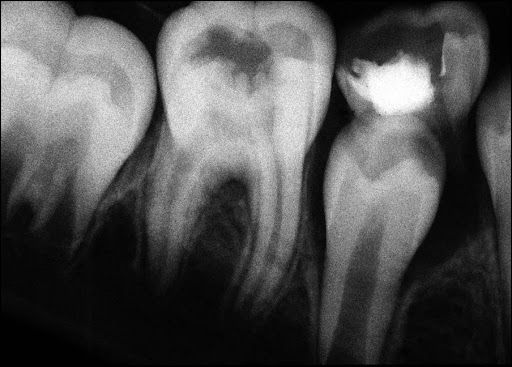

However, if a person cannot take care of his oral health, he may be subjected to several inflammations. One of those kinds of inflammation is the inflammation of the pulp. The pulp is the most inner layer of the human tooth consisting of nerves and blood vessels. Layers of enamel and dentin protect the pulp.

The pulp becomes susceptible to infections due to decay or any injury. The procedure of apexogenesis is available to treat an unhealthy tooth pulp. Apexogenesis refers to treat the flaws associated with the capping of an inflamed dental pulp of a tooth, partially developed.

In apexogenesis, the affected inflamed region of the pulp is detached and removed. The affected portion of the pulp is then infused with a material bioceramic in nature, that is, materials capable of producing a regenerative response in the body. The function of this bioceramic material is to aid the teeth in maintaining the vitality within the roots.